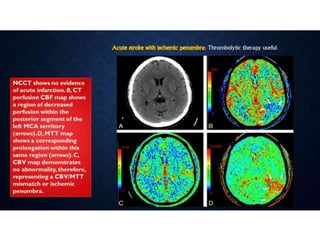

• When acute stroke patients present within 6 hours of the onset of

symptoms - un-enhanced CT or with conventional/MR imaging.

• Hemorrhage at unenhanced CT or >1/3 MCA territory - not treated

with thrombolytic drugs.

• Ischemia of < 1/3 MCA territory, those who present <3 hours after

the onset of acute stroke - intravenous thrombolytic drugs

• 3–6 hours after the onset of symptoms - CT angiography and CT

perfusion imaging to assess the intracranial and neck vessels and

detect any penumbra.

• Intraarterial therapy is usually considered for patients in whom a

penumbra is seen.

• Patients in whom no penumbra is seen are not usually treated with

thrombolytic drugs

ACUTE STROKE IMAGINGPROTOCOL • When acute stroke patients present within 6 hours of the onset of symptoms - un-enhanced CT or with conventional/MR imaging. • Hemorrhage at unenhanced CT or >1/3 MCA territory - not treated with thrombolytic drugs. • Ischemia of < 1/3 MCA territory, those who present <3 hours after the onset of acute stroke - intravenous thrombolytic drugs • 3–6 hours after the onset of symptoms - CT angiography and CT perfusion imaging to assess the intracranial and neck vessels and detect any penumbra. • Intraarterial therapy is usually considered for patients in whom a penumbra is seen. • Patients in whom no penumbra is seen are not usually treated with thrombolytic drugs